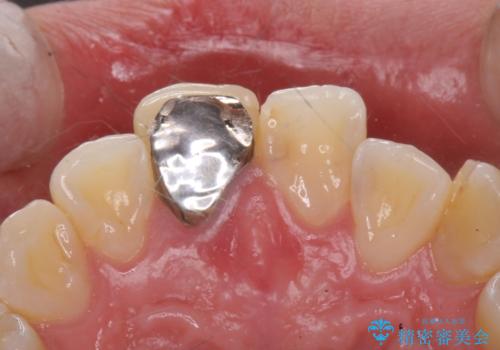

- 前歯のかぶせ物の色が気になるとのことで来院された患者様です。

セラミッククラウンで作り変えていきます。